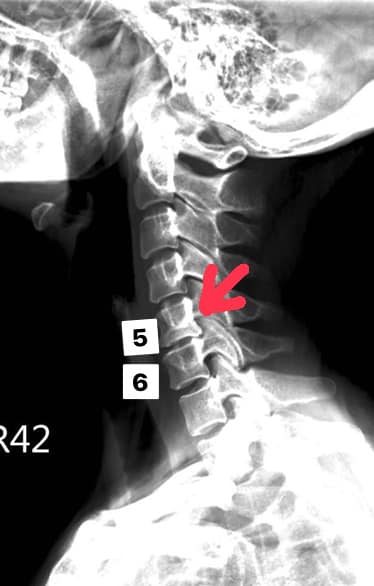

Cervical Spine Treatment Cases 頸椎治療案例 頸椎壓迫竟導致自律神經失調?耳鳴、心悸、暴瘦全因筋膜失衡! 2021.02.18 頸椎壓迫神經根導致工作受限?非手術微創療法改善關鍵公開 2021.02.17 頸椎脊髓壓迫五大症狀公開!你也有雙腳沉重、手腳麻電感嗎? 2021.01.15 長期頭痛吃藥沒效?小心你可能是「頸源性頭痛」患者 2021.01.07 #感謝新北市蘆洲區楊先生熱情見證 #頸椎病變引起肩膀痠痛無法睡眠 #曾經大痛到想立刻... 2020.12.31 #感謝新北三重劉小姐熱情見證 #神經根型頸椎病經典案例 #曾經手麻痛到無法騎摩托車 #... 2020.12.25 #遠從台東縣的熱情見證 #五個多小時的車程三百多公里很辛苦 #疼痛超過兩年打過頸椎三... 2020.12.24 #頸椎酸痛到無法睡覺是怎們回事 #醫學中心證實頸椎間盤突出 #神外醫師建議開刀但患者... 2020.12.19 #頸椎曲線弧度非常重要 #頸椎嚴重壓迫有可能逆轉嗎 #肩膀疼痛到不行合併走路都無力 #... 2020.12.09 頸椎退化壓迫神經根怎麼辦?大直林小姐四週見效的中醫微創療法 2020.12.08 #特殊案例長年過敏性鼻炎 #起因居然是頸椎交感神經筋膜壓迫 #打開椎動脈循環🔄找到解... 2020.12.05 #恭喜新店陳小姐頸椎療程畢業 #神經根型卡壓醫案 #頸椎整合中醫微創療法逆轉勝 #告別... 2020.11.24 #特殊案例頸椎手術後又再度突出案例 #感謝台中劉大哥熱情見證 #親自手捏醫師娃娃公仔... 2020.11.18 #頸椎病居然會導致手快速萎縮 #脊髓型頸椎病案例 #感謝高雄王大哥熱情見證 #頸椎整合... 2020.11.13 #神經根型頸椎病讓人痛到無法入眠 #感謝新店陳小姐熱情見證 #患者的疼痛日誌讓人感動 ... 2020.11.11 ← 上一頁 3 4 5 6 7 下一頁 →